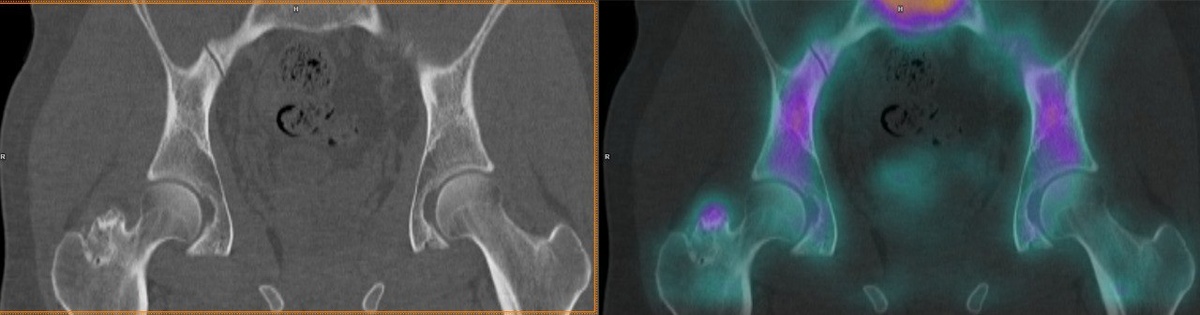

Правильный ответ на вчерашний мозговой штурм: остеохондрома

Правильный ответ на вчерашний мозговой штурм: остеохондрома.

2. Компьютерная томография (КТ):

— Что видим: КТ дает более детальное изображение костной структуры, чем рентгенография.

— Преимущества:

— Более точная оценка размеров и формы остеохондромы.

— Лучшая визуализация костной "ножки".

— Выявление обызвествлений в хрящевой "шапочке".

4. Сцинтиграфия костей:

— Что видим: Сцинтиграфия позволяет оценить остеобластическую аткивность в кости.

— Использование: Обычно используется для оценки активности роста остеохондромы или для выявления признаков злокачественного перерождения. Как правило, остеохондромы, прекратившие рост- перестают накапливать РФП.